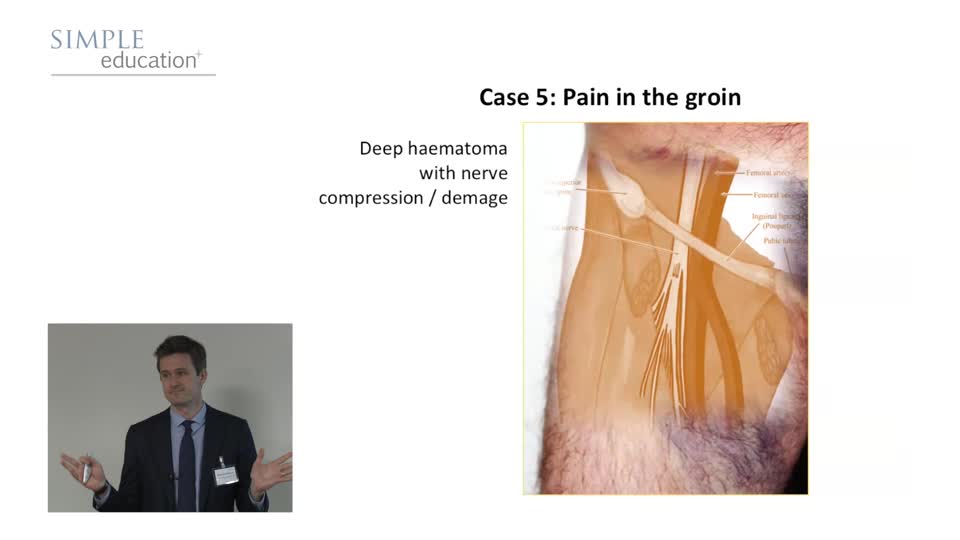

Recognise Post Angiography Problems Early and Treat Decisively - Ricardo Petraco

Simple Education